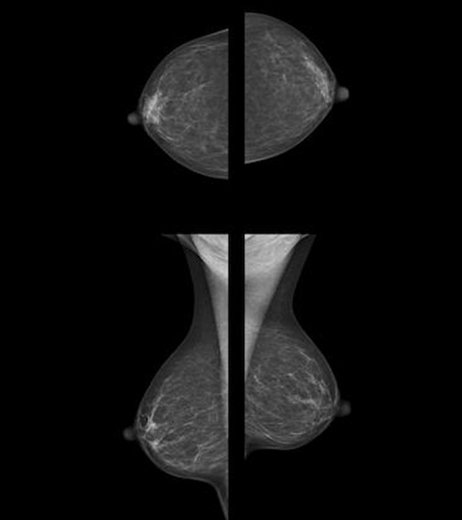

Mammografia, necessari mai còntristada quora es sistematica

Am’aquò pensa de poder afortir que l’incidéncia dau cancer dau sen aumenta en França sensa relambi , en particular amé lei fremas de pas manco quaranta ans. L’incidéncia es lo nombre de cas diagnosticats dins una annada entièra. Lo cancer dau sen tòca una frema sus uech, e chasque mes d’octòbre una campanha mediatica es bailejada tant per lei poders publics coma per leis entitats medicalas per un descobriment precòç. La dison « Octòbre ròse ».

Segons l’estudi Pujol, en trenta ans lei cancers precòç an bombats de 63% per lei fremas de trenta ans, e de 33% per lei fremas de quaranta ans. E per eu es inquiétant bòrd que lo cancer precòç sembla mai agressiu. Am’aquò lo mume a poscut dire que en trenta ans dètz milas fremas suplementarias an poscuts desvelopar un cancer dau sen.

Per apielar aqueu biais de pensar, aqueu monde se referis a la revista Cochrane qu’estudia d’estudis medicaus d’un biais sistematic. Aquela a publicat un estudi d’estudi qu’a conclús que « amb uech assajs sus 600 000 fremas de 39 a 74 ans, lo depistatge redutz la mortalitat de 15% mai que lo subrediagnostic es de 30% e podèm conclure que une frema sus 2000 convidada au depistatge serà sauve, mai que 200 autrei se veiràn en situacion de destressa psicologica e d’ànsias d’annadas a de rèng per rasons de dobtes en causa de faus positius, e que dètz seràn sonhadas d’un biais lord maugrat que siegan en bòna santat. »